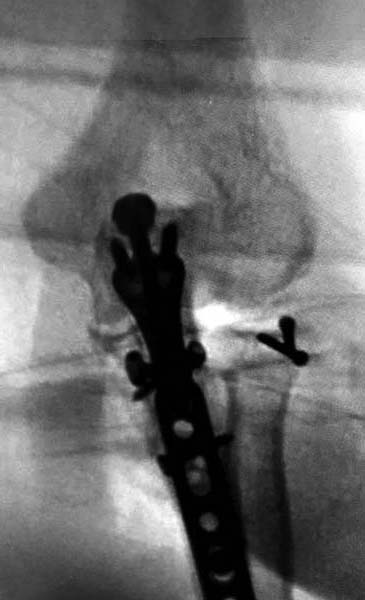

А так, здесь имеется многофрагментарный проксимальный перелом локтевого отростка с переломо-вывихом головки лучевой кости по классификации Mason III. Решение принимается на основании КТ срезов, потому что на боковом рентген снимке вроде отсутствует смещение, где сустав и контур Coronoid в одном блоке, а на прямом подозрение на смещение в Coronoid?

Для перелома локтевого отростка придуманы много пластин, надо выбрать по длине. А при краевых переломах головки ее окружность можно восстановить винтами 2 мм, но в данном случае имеется полный вывих головки и фиксация, даже специальной пластиной, может осложнится. Протез головки после удаления предупреждает нестабильность в суставе и деформацию оси конечности в будущем!

Конверсионные спицы на уровне проксимального отдела лучевой кости интересная идея, но на уровне перелома в области шейки трудно удержать головку. Предварительная репозиция локтевого отростка с временной установкой пластины, затем удаление экономит время. Доступ через локтевой отросток, где можно фиксировать или удалить головку с замещением, а потом установить пластину обратно на локтевой отросток!